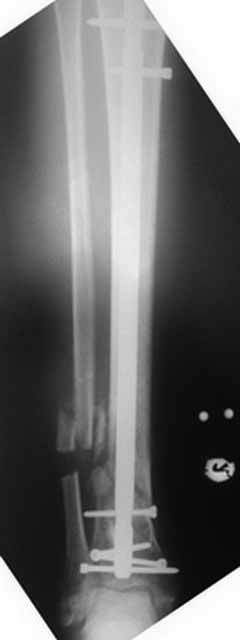

Как-то вот нет уже желания открываться в зоне ложного сустава. Мы бы

попытались сделать закрыто. Винт в дистальном отломке удалить через прокол.

Кусок гвоздя оставить. Новый гвоздь (солидный), возможно с покрытием.

Примерная ситуация. Пациент 37 лет. Синтезировали где-то пластинкой. Попал к нам через 2 месяца.

19 апреля убрали через проколы пластину с винтами, пересекли fibula, наложили аппарат.

Немного потянули по оси, убрали вальгус, ротацию. 22 апреля (на 3-е сутки) заштифтовали окончательно. 29 апреля выписали из отделения. На все ушло 10 дней.